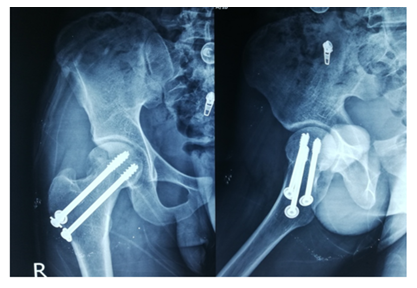

The screw lengths are measured, and drilling is performed using a 4.5 mm cannulated reamer. The screws are then inserted (for the BDSF technique, a specific sequence of middle, then superior, and lastly inferior screw insertion is to be followed). All three screws are inserted less than 5 mm subchondrally (Figure 3,4). In all cases, a prophylactic antibiotic was given. In the postoperative ward, proper fluid and hemodynamic balance were ensured. Change of posture was done twice an hour. The antibiotic was continued for 3 days. Analgesics were given to ensure a pain-free postoperative period. On the first postoperative day, patients were allowed to sit on the side of the bed. Patients were being educated about breathing exercises, isometric quadriceps exercises, gluteal exercises, and ankle pumping exercises. An immediate postoperative X-ray was done (Figure 5). After checking the dressing, on 4th POD, they were discharged from the hospital if their postoperative period was uneventful. Oral antibiotics were given for 10 days. Advice was given to continue isometric quadriceps exercise. Regarding ambulation, they were advised to do non-weight-bearing (of the affected side) crutch ambulation until directed by the physician. Use of elevated toilet seats onwards is also advised. The next follow-up would be given at the 14th POD. The first follow-up was given at 14th POD to check any signs of infection, pain status, and distal neurovascular status. The stitch was removed on the same day. Advice given about isometric quadriceps exercise, active abduction, extension exercise, and stretching exercise of the hip joint. The next follow-up was the 6th week after the operation. The range of motion was tested. An X-ray was done to check callus formation. Improvements were noted. Partial weight bearing was given at this follow-up. Subsequent follow-up was given at 12 weeks and every 4 weeks until union has been achieved or at least 9 months (Figures 6-10).